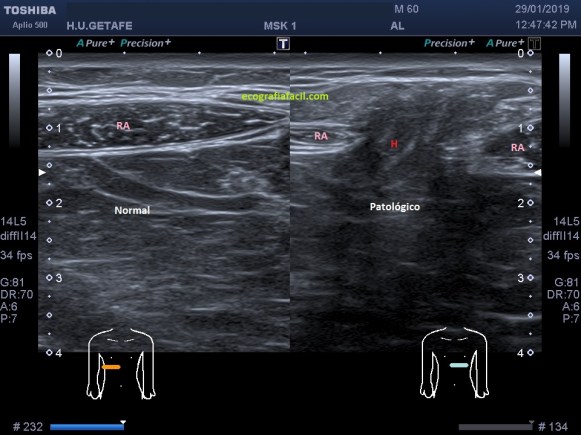

Vamos a partir de la normalidad y te vienes a ver ahora la patología que hoy nos ocupa, mira. En ocasiones podemos encontrarnos la imagen patológica que indica luxación del tendón, imagen 2. Es un corte en Eje corto. Ves la corredera bicipital vacía, el tendón fuera de su localización habitual, hacia medial, como es habitual, pero conservando la ecoestructura.

La imagen número 3 corresponde al corte en eje largo, mucho cuidado, siempre que tengamos el tendón del bíceps luxado, este se irá hacia medial, por eso, en eje largo vamos a encontrar la ecoestructura ligeramente hacia la axila, hacia medial.